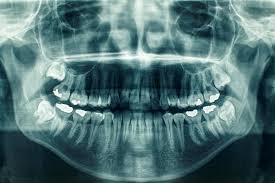

Panoramic Taken On Our Office On A 10 Year Old Child Showing Permanents As Well As Primary Teeth Unerupted Dental Treatment Dental Clinic Dental